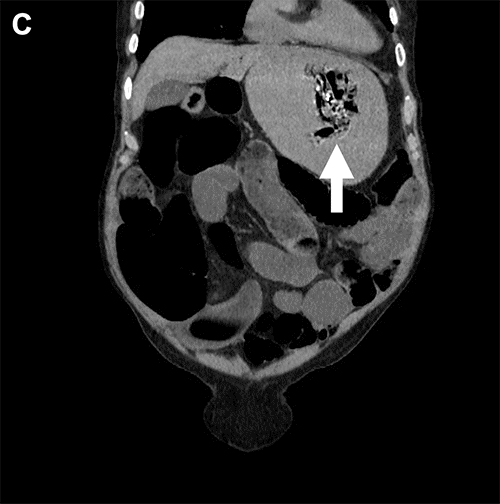

At the initial examination, the patient was alert, oriented, and complaining of severe abdominal pain. He was hypertensive with otherwise normal vital signs and a body mass index of 22. His abdomen was distended, tympanic, and diffusely tender. His laboratory tests included a white blood cell count of 14,400 per µL, a serum bicarbonate of 15 mEq/L, and a serum lactate of 6 mmol/L. Attempts at nasogastric tube placement were unsuccessful secondary to resistance during insertion. A computerized tomography (CT) scan obtained in the emergency department demonstrated (i) markedly dilated loops of small bowel with a transition point in the distal ileum, (ii) portal venous gas, (iii) a small ventral hernia containing a non-obstructed loop of colon, and (iv) a foreign body (possibly a bezoar) freely floating within the lumen of a distended, intraabdominal stomach (Figure 1).

Figure 1. Preoperative CT. Published with Permission

A) Cross-sectional view, upper abdomen. Large arrow = free-floating mass within lumen of stomach. Small arrows = portal venous gas

B) Sagittal view, left side

C) Coronal view, anterior